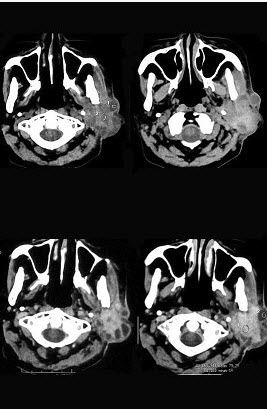

女,55岁,鼻咽癌放疗15年,近一周左耳根部肿胀,无发热,PE://左耳根部皮下扪及三个结节,有波动感和轻压痛,CT如图所示,最可能的诊断是()。

A、左腮腺腺瘤

B、左腮腺混合瘤

C、左腮腺腺淋巴瘤

D、左腮腺恶性混合瘤

E、左腮腺蜂窝织炎

正确答案:

E

答案解析: